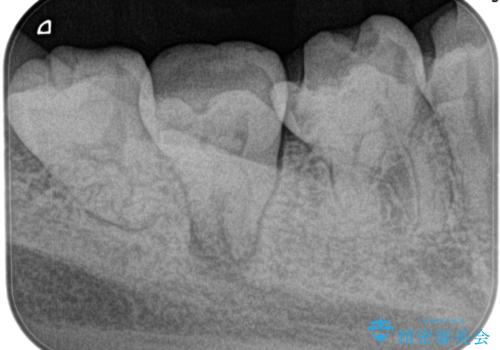

定期検診にて膿の出口を見つけた。精密根管治療

- 定期検診にて膿の出口を見つけたことを主訴に来院されました。

検査の結果、診断を歯髄壊死、症候性根尖性歯周炎とし抜髄を行っております。

根管充填はCWCTにて行なっています。